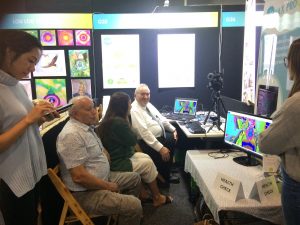

ERIC was first publicly demonstrated at the Mind, Body and Spirit festival this year where it received outstanding praise for its simplicity in being able to diagnose peoples health conditions. Over 50 people volunteered to see how ERIC could detect changes within them from different treatments, meditations, foods, and healings, with many before and after photos being taken to verify that changes have actually occurred.

The pictures show the camera in operation, the before and after pictures.

The Camera (ERIC) was first shown to the public during the Mind, Body and Spirit festival in March 2020, with great success.